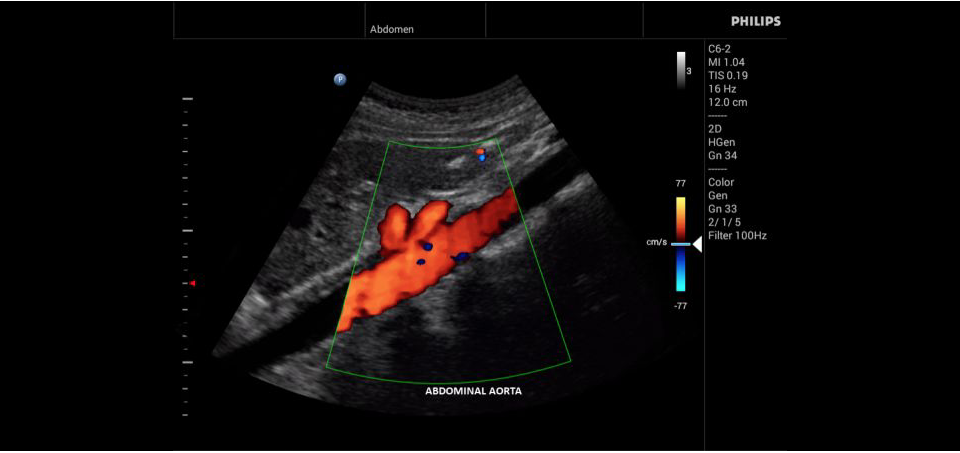

УЗИ-аппарат

Philips InnoSight

Philips InnoSight увеличивает возможности сканирования во множестве мест оказания медицинских услуг. Благодаря данному УЗИ аппарату врачи могут не сомневаться в быстром выполнении обычных ультразвуковых сканирований во врачебном кабинете, клинике или больнице.

InnoSight позволяет перенести ультразвуковую диагностику непосредственно туда, где пациенту оказывается медицинская помощь, что повышает мобильность врачей. Этот компактный и легкий ультразвуковой аппарат позволяет чаще использовать возможности ультразвуковой диагностики и предоставляет широкий набор технологий для проведения углубленных исследований — программные пакеты для специализированного анализа, функции аннотирования и наборы готовых настроек для различных типов тканей.

Эргономичная система с высококачественными широкополосными датчиками Philips помогает повысить клиническую надежность результатов исследования и уровень оказания медицинских услуг. Аппарат можно перемещать вручную или с помощью тележки.

• Общие абдоминальные исследования;

• Исследования сосудов;

• Цветное допплеровское картирование